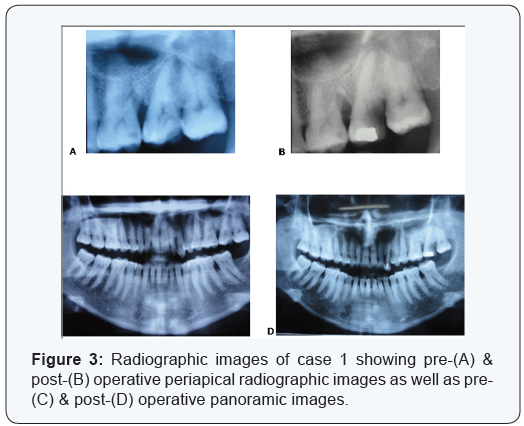

Two cases are presented in figures from 2 to 5 with clinical photographs during surgical intervention and pre-& postoperative radiographic images. Case 1 is presented in figures ( 1 & 3) and was treated by using bio absorbable equine collagen membrane, for covering and treatment of selected intrabony defect site between teeth No. 26 & 27 as mainly distal to tooth No. 26. Case 2 is presented in ( figures 4 & 5 ) and was treated by the application of the same bio absorbable collagen membrane but in combination with equine bone as xenograft material, for covering and treatment of selected intrabony defect site between teeth No. 35 & 36 as mainly mesial to tooth No. 36.

Standardized intra-oral periapical radiographs (Kodak X-ray film, USA) were obtained at baseline and 18 months postoperatively. These radiographs were taken using long cone/ extension cone paralleling technique with a positioning device mounted on a roentgen machine, operating at 70 Kilo Voltage Power.

Radiographs were scanned using a digital scanner at an input of 300 dpi and 100% scale, then they were analyzed using a software@. The images had 768 × 512 pixels and 256 gray scale level. The alignment of images, in the pairs of radiographs, was applied to correct small geometric misalignments. Gray level was then calibrated to indicate changes in the radiographic density (RD).

In addition, the following measurements were obtained in millimeters: distance from cementoenamel junction (CEJ) to base of the defect (BD) and from CEJ to alveolar crest (AC). The differences between baseline and 18-month postoperative values for CEJ–BD indicated the change in the radiographic defect depth (RDD), whereas the differences for CEJ–AC suggested the possible occurrence of crestal bone resorption (CBR).